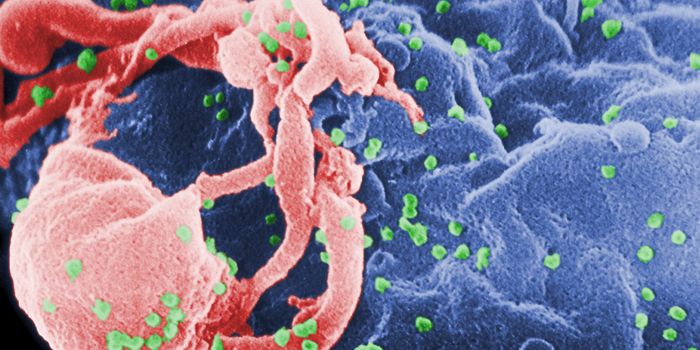

NOV 10, 2019MicrobiologyFor the first time since 2000, researchers have identified a new subtype of HIV.

FEB 02, 2016MicrobiologyUniversity of Minnesota researchers found a new, more affordable way to treat HIV. The RNA-based drug 5-azacytidin ...

DEC 15, 2018Cell & Molecular BiologyResearchers have been trying to create a vaccine for HIV, the virus that causes AIDS, for decades.